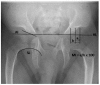

Mucolipidosis type II (MLII) is a rare lysosomal storage disorder caused by defective trafficking of lysosomal enzymes. Severe skeletal manifestations are a hallmark of the disease including hip dysplasia. This study aims to describe hip morphology and the natural course of hip pathologies in MLII by systematic evaluation of plain radiographs, ultrasounds and magnetic resonance imaging (MRI). An international two-centered study was performed by retrospective chart review. All MLII patients with at least one pelvic radiograph were included. A total of 16 patients were followed over a mean of 3.5 years (range 0.2-10.7 years). Typical age-dependent radiographic signs identified were femoral cloaking (7/16), rickets/hyperparathyroidism-like changes (6/16) and constrictions of the supra-acetabular part of the os ilium (16/16) and the femoral neck (7/16). The course of acetabular and migration indexes (AI, MI) significantly increased in female patients. However, in the overall group, there was no relevant progression of acetabular dysplasia with a mean AI of 23.0 (range 5°-41°) and 23.7° (range 5°-40°) at the first and last assessments, respectively. Better knowledge on hip morphology in MLII could lead to earlier diagnosis, improved clinical management and enables assessment of effects of upcoming therapies on the skeletal system.